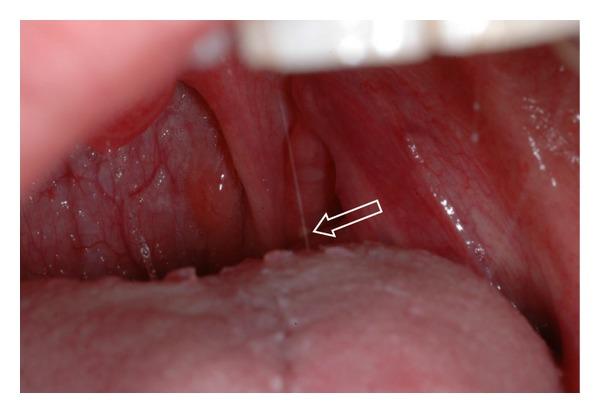

Objective. The purpose of this study was to determine the prevalence of tonsiliths in patients attending the oral and maxillofacial radiology clinic of The University of Iowa and to determine if there is any correlation between the presence of tonsiliths and the presence of stones in other body tissues, ducts, or organs. Study Design. This was a two-part study. The first part was a prevalence study whereas the second was a matched pair case-control study. The matched pair case-control study commenced after the prevalence study was concluded. No new or unusual radiographs were made in this study. The study only reviewed radiographs that were made for clinical purposes. Results. A total of 1524 pantomographs were reviewed and 124 subjects (53 males and 71 females) aged 9 years and 2 months to 87 years (mean age 52.6 years) were included for data analysis. Thirty-eight subjects had single tonsiliths whereas 86 subjects had multiple tonsiliths. The prevalence of tonsiliths in the study population was 8.14%. A total of 20 subjects were included in the second part of the study, comprising 10 each for matched pair case-control groups. The observations did not indicate any correlation between the presence of tonsiliths and the presence of stones in other body tissues, ducts, or organs. Conclusion. The prevalence of tonsiliths in our study population was 8.14%. The observations in our study do not support any correlations between tonsiliths and calcifications in other body tissues, organs, or ducts.

目的。本研究的目的是确定就诊于爱荷华大学口腔颌面放射科诊所的患者中扁桃体结石的患病率,并确定扁桃体结石的存在与其他身体组织、导管或器官中结石的存在之间是否存在任何关联。研究设计。这是一项分为两部分的研究。第一部分是患病率研究,而第二部分是配对病例对照研究。配对病例对照研究在患病率研究结束后开始。本研究未拍摄新的或特殊的X光片。该研究仅回顾了出于临床目的拍摄的X光片。结果。共回顾了1524张全景片,纳入124名年龄在9岁2个月至87岁(平均年龄52.6岁)的受试者(53名男性和71名女性)进行数据分析。38名受试者有单个扁桃体结石,而86名受试者有多个扁桃体结石。研究人群中扁桃体结石的患病率为8.14%。研究的第二部分共纳入20名受试者,配对病例对照组各10名。观察结果未表明扁桃体结石的存在与其他身体组织、导管或器官中结石的存在之间存在任何关联。结论。我们研究人群中扁桃体结石的患病率为8.14%。我们研究中的观察结果不支持扁桃体结石与其他身体组织、器官或导管中的钙化之间存在任何关联。